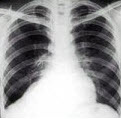

18、单项选择题

男,69岁,咳嗽,胸痛2月余,胸片检查如图,最可能的诊断为()

A.血行播散型肺结核

B.肺转移瘤

C.两肺炎症

D.细支气管肺泡癌

E.结节病

点击查看答案